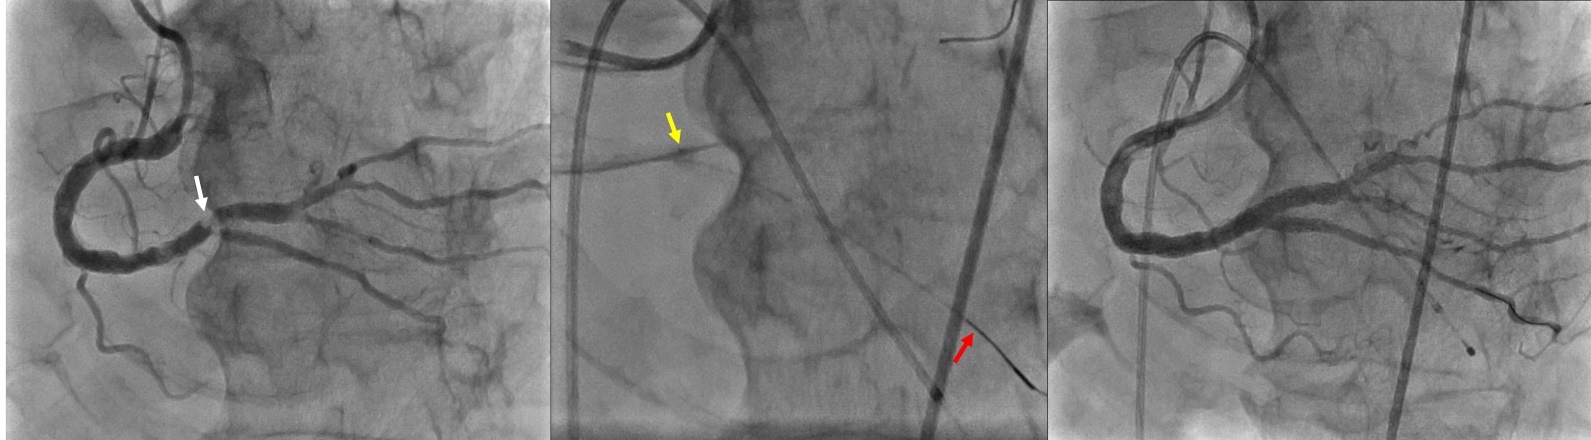

Case: A 74-year-old male with a recent NSTEMI presented for elective coronary artery revascularization. A coronary angiogram revealed non-obstructive left coronary arteries and a dominant right coronary artery (RCA) with heavily calcified stenosis at the bifurcation of the right posterolateral (RPL) and right posterior descending (RPD) branches. After placing temporary transvenous pacing and inserting sheaths in the right radial and right femoral arteries, both the RPL and RPD were wired with coronary guidewires. Using a coronary microcatheter, the wire in RPL was replaced with a ViperWire guidewire for OA, while the microcatheter in RPD served as guidewire protection. OA of RPL was successfully performed with the Diamondback 360° OA system (Cardiovascular Systems Inc), followed by multiple dilatations with non-compliant balloons and placement of two drug-eluting stents in the distal RCA to RPL and RPD, achieving good angiographic and IVUS results.

Discussion: The Double Guiding Catheter Technique has been described in a few case reports of heavily calcified left main coronary bifurcation atherectomy which is limited to relatively proximal lesions due to the need to pass a second wire to a non-atherectomy vessel outside a guide extension catheter for the main branch. This is the first reported case of OA using this technique in the right coronary artery and a relatively distal part of the coronary artery. The primary advantage of this technique is eliminating the need to withdraw one of the two wires, which can be challenging when recrossing the side branch. The microcatheter can safely protect the other branch wire during atherectomy.

Conclusion: By maintaining both wires with a protective microcatheter, OA of coronary bifurcation stenosis can be successfully achieved, potentially reducing the risk of wire transection.